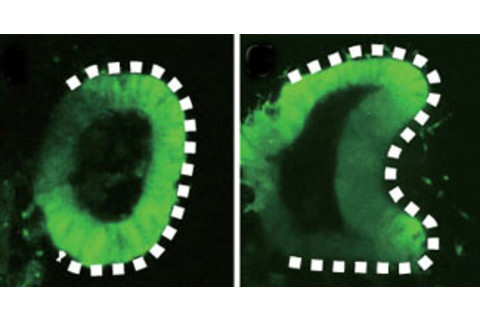

The stem cells formed a sac that then folded in half a couple days later (see image above, courtesy of Nature), forming the optic cup.

). “I never though I'd see the day where you have recapitulation of development in a dish." How the Heck: Supported by a gel that mimics cells’ natural environment, the stem cells were immersed in a bath of chemicals that directed their growth into retinal cells. Just as in normal embryonic development, over the course of about a week the cells organized themselves into a small sac that spontaneously folded itself in half to form the optic cup, a structure that consists of the retina and its supporting layer. What’s the Context: